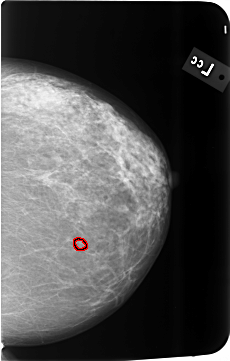

B_3493_1.LEFT_CC

LEFT_CC LINES 5776 PIXELS_PER_LINE 3672 BITS_PER_PIXEL 12 RESOLUTION 50 OVERLAY

FILE: B_3493_1.LEFT_CC.OVERLAY

TOTAL_ABNORMALITIES 1

ABNORMALITY 1

LESION_TYPE CALCIFICATION TYPE PLEOMORPHIC DISTRIBUTION CLUSTERED

ASSESSMENT 4

SUBTLETY 3

PATHOLOGY BENIGN

TOTAL_OUTLINES 1

BOUNDARY